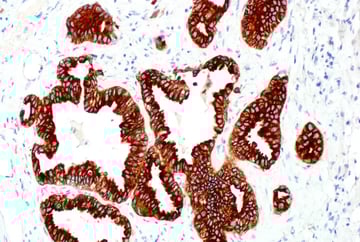

| IHC analysis of paraffin-embedded human non-small cell lung carcinoma using ALK (D5F3®) Rabbit Monoclonal Antibody #3633. | IHC analysis of paraffin-embedded human lung carcinoma using ROS1 (D4D6®) Rabbit Monoclonal Antibody #3287. |

After binding a ligand, RTKs undergo phosphorylation at their cytoplasmic tails (C-termini), which initiates the intracellular signaling. Oncogenic mutations and gene fusions involving RTK kinase domains—for example, CD74‑ROS1, SLC34A2‑ROS1, EML4‑ALK, and NPM‑ALK—can create abnormally active receptors that drive tumor growth. Additionally, in some types of cancer, RTK domains can become uncoupled from the membrane receptor and instead signal in the cytoplasm, allowing them to remain active without growth factor binding or Ras activation.